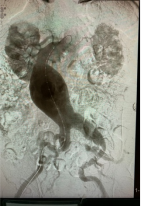

腹主动脉瘤手术方式包括:1、外科开腹人工血管置换手术。开腹手术面对已出现渗漏的腹主动脉瘤治疗有方便止血优势,但手术创伤大,需要输血,病人不易耐受。2、微创介入腔内覆膜支架植入术。腹主动脉覆膜支架腔内隔绝术手术的优点是降低围手术期死亡率,合并多基础病的腹主动脉瘤患者更容易耐受,潜在优点包括降低手术耗时、减轻疼痛和创伤、缩短住院时间和外科监护时间、减少输血。